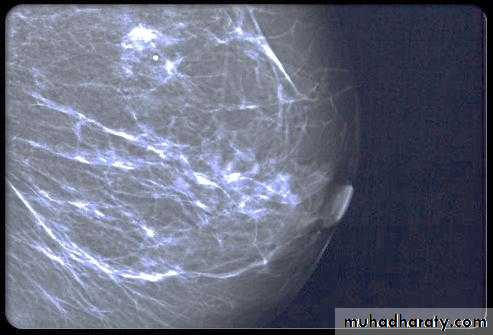

A…..Invasive ductal carcinoma is a subset of ductal carcinoma. It is an infiltrating, malignant and abnormal proliferation of neoplastic cells in the breast tissues. It is the most frequently seen breast malignancy .

Radiographic features

Mammogram

spiculated hyperdense lesion

oval/lobulated lesion

microcalicifications